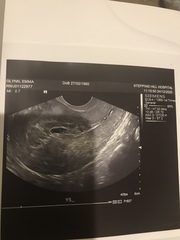

So here’s my scan from Xmas eve. Bleeding got worse and pain like period cramps. It’s not soaking through pads but get a trickle when I go to the loo. They said only measuring 5 weeks but i was 7+2 and couldn’t see a heartbeat. She said sac was a little too close to my C section scar which was worrying. I’ve tried to make sense of my ultrasound from what tech said but she said it was a pregnancy of uncertain viability and to return for a scan in 2 weeks. I went to a different EPU as mine couldn’t see me but I have an early scan already booked on the 2nd which will no doubt confirm the miscarriage

Can anyone make sense of my scan ?